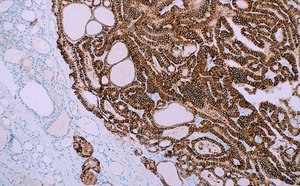

From consistent routine and special stains, to reliable Cell Marque™ IHC primary antibodies, universal reagents, control slides and cell lines, we provide efficient, precise solutions for research and clinical pathology laboratories. We developed trusted staining solutions and ready-to-use test kits, as well as Biological Stain Commission (BSC) certified dyes, centrifugation media, and in vitro diagnostics immunohistochemistry (IHC) antibodies and reagents.

Our complete line of solvents and fixatives for microscopy sample preparation, mounting media for routine and fluorescent applications, and tissue quality control slides allows increased stability, ease of use, and reproducibility of results. Our products are manufactured following cGMP practices, and our IVD stains and kits comply with ISO 13485 and CFR 820. Our pathology lab reagents are IVD-registered and CE-certified where required.

Cell Marque™ products are trusted worldwide in clinical pathology, including IVD and IHC applications. Browse our vast selection of specialty antibodies, reagents, and control slides.

Browse our comprehensive tissue diagnostics and microscopy portfolio with routine, special, and advanced staining solutions for hematology, cytology, histology and bacteriology.